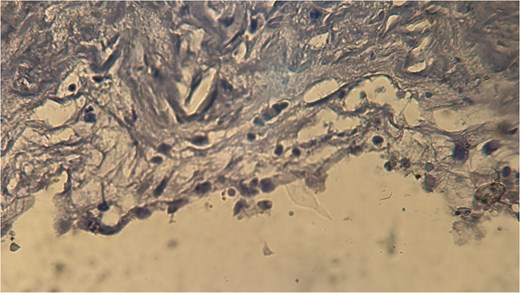

A 60-year-old Moroccan female with no significant medical history presented with chronic periumbilical pain lasting several months, without associated digestive or systemic symptoms, and preserved general condition. Clinical examination revealed periumbilical tenderness. Abdominal ultrasound was unremarkable, prompting an abdominopelvic CT scan, which identified a retroperitoneal inter-aortocaval cystic lesion measuring 86 mm. Surgical exploration revealed a large cystic mass in the mesentery of the small intestine, which was entirely excised. Histopathological examination showed variable-sized cystic cavities with a lymphatic appearance (Fig. 1), lined by flattened and regular endothelium. Some cavities contained pale eosinophilic material interspersed with lymphocytes and areas of red blood cells (Fig. 2). The interstitial tissue exhibited lymphocytic and plasmacytic inflammatory infiltrates. Immunohistochemistry confirmed the lymphatic nature with positivity for Podoplanin/D2–40 (Fig. 3) and CD34 (Fig. 4) and negativity for calretinin (Fig. 5). The patient’s postoperative course was uneventful.

Eosinophilic material and inflammatory infiltrates composed of lymphocytes and red blood cells.